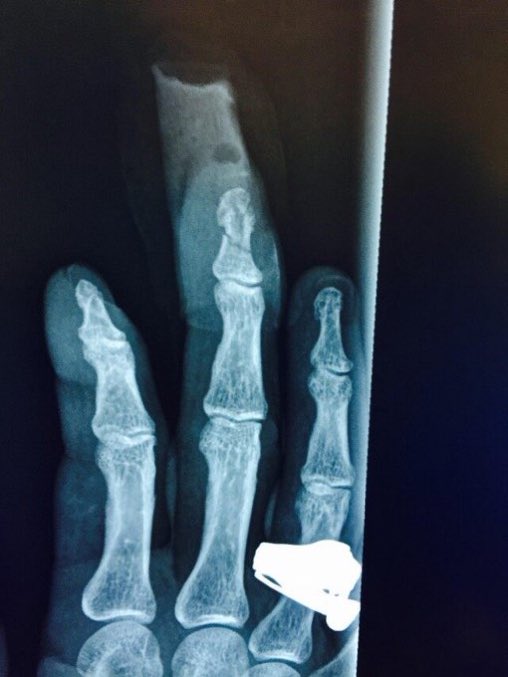

صرح جوني أنه عندما كان بشهر العسل مع آمبر في أستراليا في عام 2015 وبشهر مارس قامت آمبر برمي زجاجة الفودكا عليه وقطعت جزء من أصبعه وأطفت سجارة على خده الأيمن.